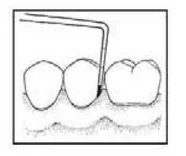

Instrumentem przedstawionym na ilustracji stosowanym w chirurgii stomatologicznej jest